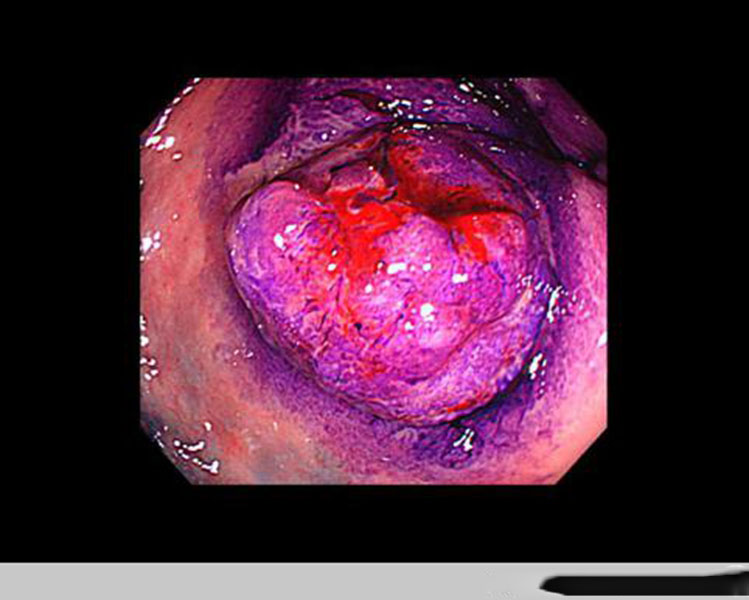

腸腫瘤圖片

直腸腫瘤惡性腸鏡

直腸腫瘤

直腸腫瘤早期